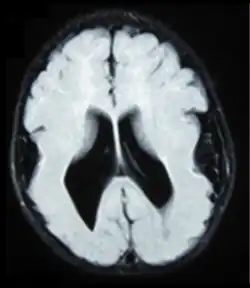

- Radiological findings (MRI) demonstrated symmetric generalized polymicrogyria with decreasing anterior-posterior gradient, most prominent in frontoparietal cortex.[5]

- Numerous gyrus on the cortex

- Small gyri and sulci

- Thin cortex

There are different tests or methods used to determine GPR56 expression or visuals of the brain to analyze the specific sections that are affected. These tests for example, using animals such as mice, RNAi, Behavioral assay, Electron microscopy, CT scan, or MRI demonstrate different results that concludes an affected BFPP patient.[15] MRI's reveal either irregularity to the cortical surface suggestive of multiple small folds or an irregular, scalloped appearance of the gray matter-white matter junction.

Neuroimaging

The diagnosis of polymicrogyria is typically made by magnetic resonance imaging (MRI) since computed tomography (CT) and other imaging methods generally do not have high enough resolution or adequate contrast to identify the small folds that define the condition. The cerebral cortex often appears abnormally thick as well because the multiple small gyri are fused, infolded, and superimposed in appearance.[5]

Neuropathology

Gross neuropathologic examination reveals a pattern of complex convolutions to the cerebral cortex, with miniature gyri fused and superimposed together, often resulting in an irregular brain surface. The cortical ribbon can appear excessively thick as a result of the infolding and fusion of multiple small gyri.[5]

Microscopic examination demonstrates that the cerebral cortex is in fact abnormally thin and has abnormal lamination; typically the cortex is unlayered or has four layers, in contrast to the normal six layers. The most superficial layers between adjacent small gyri appear fused, with the pia (layer of the meninges) bridging across multiple gyri. Prenatal diagnosis for BFPP is also available for pregnancies at risk if the GPR56 mutations have been identified in an affected family member.[5]